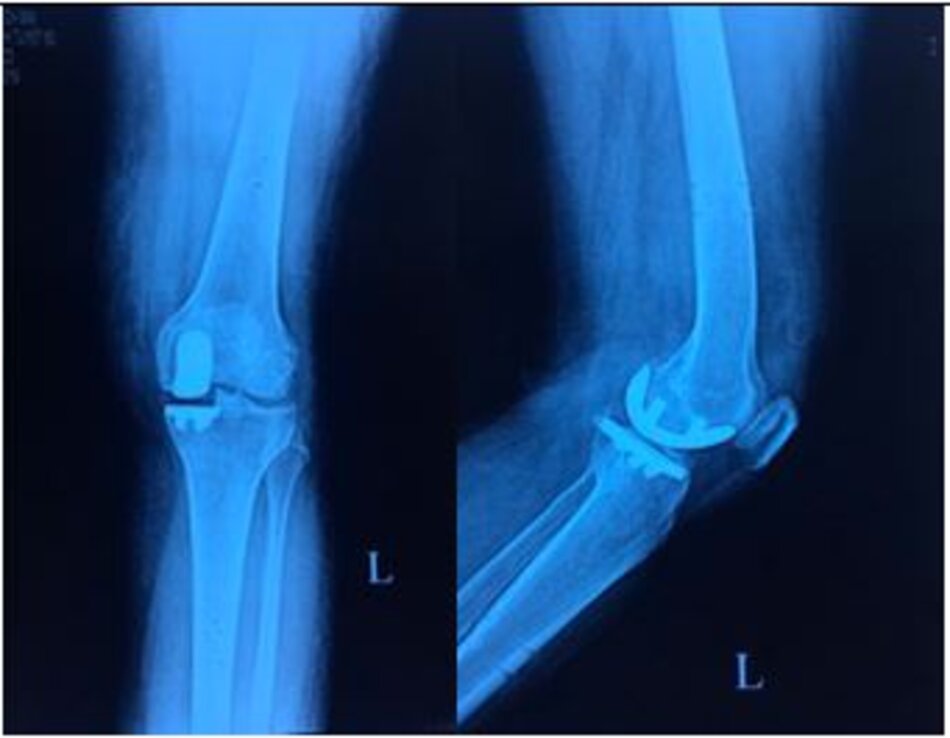

Thay khớp gối

Phẫu thuật thay khớp gối điều trị thoái hoá khớp gối giai đoạn cuối

Bệnh nhân nữ 68t, Gối phải đau, đi lại < 200 m, phẫu thuật thay khớp gối toàn bộ, sau mổ 3 ngày bệnh nhân được tập đi có khung hỗ trợ.

X-quang trước mổ và sau mổ bệnh nhân thay khớp gối toàn phần do thoái hoá